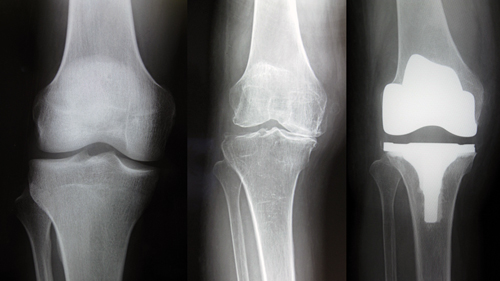

左:正常 中央:変形性膝関節症 右:人工膝関節置換術